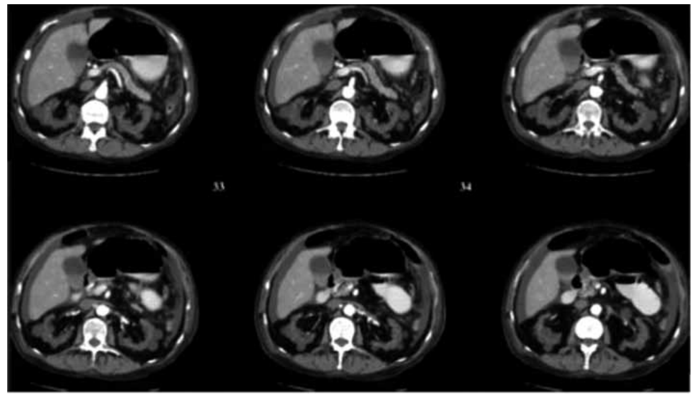

Homem de 72 anos em tratamento dialítico há 8 anos por doença renal crônica de etiologia indeterminada. Refere ter

apresentado um episódio de hematúria macroscópica há 2 dias, associado a dor lombar. Usou analgésico, com melhora

parcial. Tomografia de abdome com imagem a seguir.

(Arquivo pessoal; imagem usada com autorização)